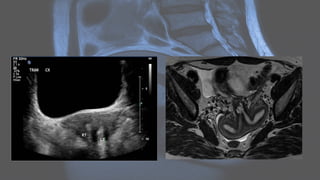

Adenomyosis • Adenomyosis (oruterine adenomyosis) is a common uterine condition of ectopic endometrial tissue in the myometrium, sometimes considered a spectrum of endometriosis. Although most commonly asymptomatic, it may present with menorrhagia and dysmenorrhea. • Pelvic imaging (i.e. ultrasound, MRI) may show characteristic findings, commonly including focal or diffuse myometrial bulkiness, which may be asymmetrical, and heterogeneous myometrium.

USG • A "Venetianblind" or "rain shower" appearance (linear striations, parallel shadowing) may be seen as a combination of the aforementioned features: heterogeneous 1,2,20, coarsened echotexture of the myometrium, and acoustic shadowing where endometrial tissues cause a hyperplastic reaction. The combination of this heterogeneity and the subendometrial echogenic nodular and linear striations is not dissimilar to the appearance of chronic liver parenchymal disease - hence, “cirrhosis of the uterus.”